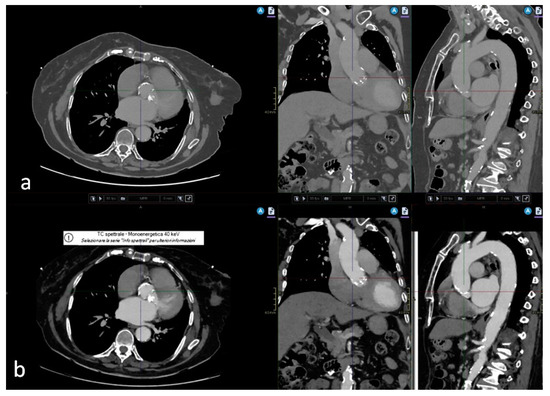

Reduced iodine loads for computed tomography (CT)-based vascular assessment prior to transcatheter aortic valve implantation (TAVI) may be feasible in conjunction with a spectral detector CT scanner. This prospective single-center study considered 100 consecutive patients clinically referred for pre-TAVI CT. They were examined [...] Read more.

Reduced iodine loads for computed tomography (CT)-based vascular assessment prior to transcatheter aortic valve implantation (TAVI) may be feasible in conjunction with a spectral detector CT scanner. This prospective single-center study considered 100 consecutive patients clinically referred for pre-TAVI CT. They were examined on a dual-layer detector CT scanner to obtain an ECG-gated cardiac scan and a non-ECG-gated aortoiliofemoral scan. Either a standard contrast media (SCM) protocol using 80 mL Iohexol 350 mgI/mL (iodine load: 28 gI) or a body-mass-index adjusted reduced contrast media (RCM) protocol using 40–70 mL Iohexol 350 mgI/mL (iodine load: 14–24.5 gI) were employed. Conventional images and virtual monoenergetic images at 40–80 keV were reconstructed. A threshold of 250 HU was set for sufficient attenuation along the arterial access pathway. A qualitative assessment used a five-point Likert scale. Sufficient attenuation in the thoracic aorta was observed for all patients in both groups using conventional images. In the abdominal, iliac, and femoral segments, sufficient attenuation was observed for the majority of patients when using virtual monoenergetic images (SCM: 96–100% of patients, RCM: 88–94%) without statistical difference between both groups. Segments with attenuation measurements below the threshold remained qualitatively assessable as well. Likert scores were ‘excellent’ for virtual monoenergetic images 50 keV and 55 keV in both groups (RCM: 1.2–1.4, SCM: 1.2–1.3). With diagnostic image quality maintained, it can be concluded that reduced iodine loads of 14–24.5 gI are feasible for pre-TAVI vascular assessment on a spectral detector CT scanner. Full article

Show Figures

Figure 1